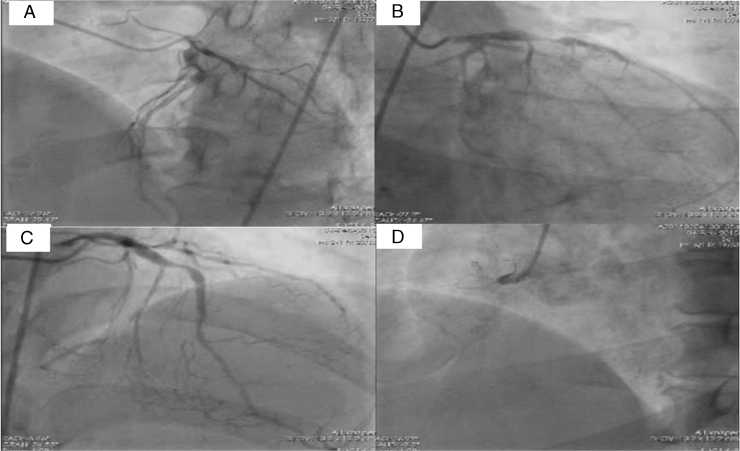

Figure 2.

Coronary angiogram in A: left anterior oblique cranial, B: right anterior oblique caudal, and C: cranial views showing significant lesions in proximal left anterior descending artery. D: The right coronary artery was totally occluded at the proximal segment.

A 55-year-old diabetic and hypertensive man presented with 3 episodes of syncope, all in upright posture, in the previous 1 and half years. He denied a history of angina, palpitation, or dyspnea at any time, including prior to the episodes. The patient was hospitalized after each episode and his vital signs, electrocardiogram, and blood sugars were found to be normal. He had no postural fall in blood pressure, carotids were normal, and no evidence of carotid hypersensitivity was noted. Echocardiogram was normal and Holter monitoring did not reveal any significant pause or arrhythmia. With the possibility of neurocardiogenic syncope, HUTT was performed using the Italian protocol.2 Briefly, the procedure was performed in the morning, after overnight fasting in a quiet, slightly darkened room that had resuscitative equipment, and was monitored by a cardiology resident and staff nurse. The tilt test was performed by means of an electronically controlled tilt table with a footboard for weight bearing. Restraining belts were placed at chest and thigh levels. Blood pressure, heart rate, and rhythm were continuously monitored using limb lead 2, and were recorded every 2−5 minutes, or more often if symptoms developed. Head-up tilt was performed after an initial observation with the patient in the supine position for 10 minutes. The test consisted of 2 consecutive phases; during the first phase, the patient was tilted at 60 degrees for up to 45 minutes without medication. Since baseline tilt did not induce syncope, the second phase of the test was repeated with the patient being tilted to 60 degrees after 300 mcg of sublingual NTG. After 5 minutes of upright tilt, the patient developed syncope, associated with abrupt sinus pause that continued for 9 seconds (Figure 1A and B), and as the patient was being lowered to supine position this was followed by a brief episode of ventricular fibrillation (VF) (Figure 1C). While the defibrillator was being readied to deliver a DC shock, external cardiac massage was being instituted and the VF terminated without the necessity of a DC shock (Figure 1D), first for a brief period of asystole followed by resumption of sinus rhythm. Subsequently, a treadmill test was performed on Bruce protocol to evaluate for coronary artery disease, which was strongly positive for inducible ischemia at 4 minutes of exercise, with no angina during the test. Coronary angiogram was performed and revealed triple vessel coronary artery disease (Figure 2A−D), for which the patient underwent successful coronary artery bypass surgery. At 2 months postsurgery, the patient underwent a repeat tilt table test, but this time with a hands-free defibrillator with external pacing capability applied to the chest wall. The test was positive, with an asystolic response of 6 seconds with no episode of VF. It was decided to manage the patient with conservative therapy with lifestyle modification and consider pacing if there were frequent recurrences of syncope. At 3 months postsurgery the patient has been free of syncopal episodes. Since the patient had a reversible cause of VF and normal ventricular function, an implantable cardioverter-defibrillator (ICD) was not considered.